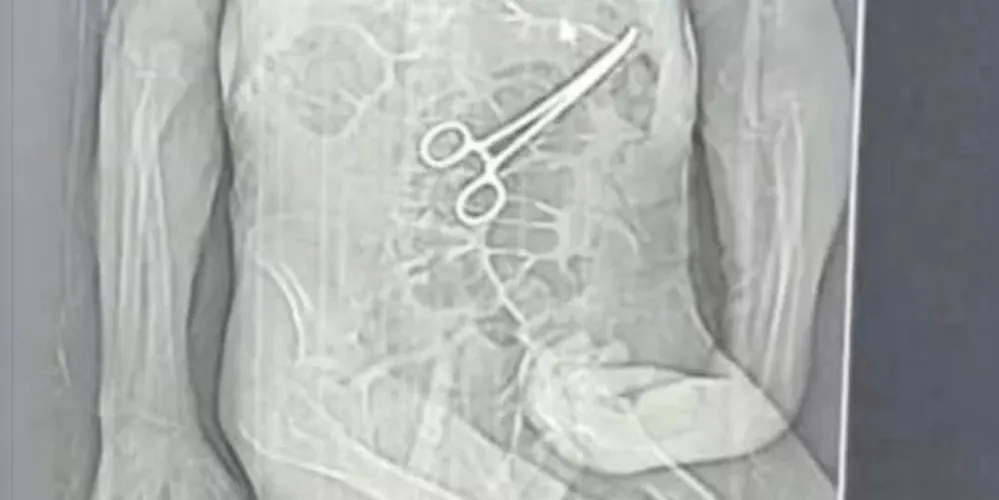

Após a morte, a família teve conhecimento de uma tomografia divulgada por uma rádio local que indicaria a presença de uma pinça cirúrgica dentro do corpo do paciente. Segundo o advogado dos familiares, Iuri Evangelista Furtado, a partir desse exame começaram a ser adotadas medidas legais.

Um homem, de 68 anos, morreu na véspera do Natal, após passar por duas cirurgias no Hospital Municipal de João Pinheiro, no noroeste de Minas Gerais. A família de Manoel Cardoso de Brito acusa a unidade de saúde de erro médico e afirma que uma pinça cirúrgica foi esquecida dentro do corpo do paciente após o primeiro procedimento.

A Secretaria Municipal de Saúde confirmou que houve a retirada de um corpo estranho durante a cirurgia e informou que abriu uma sindicância para apurar o caso.